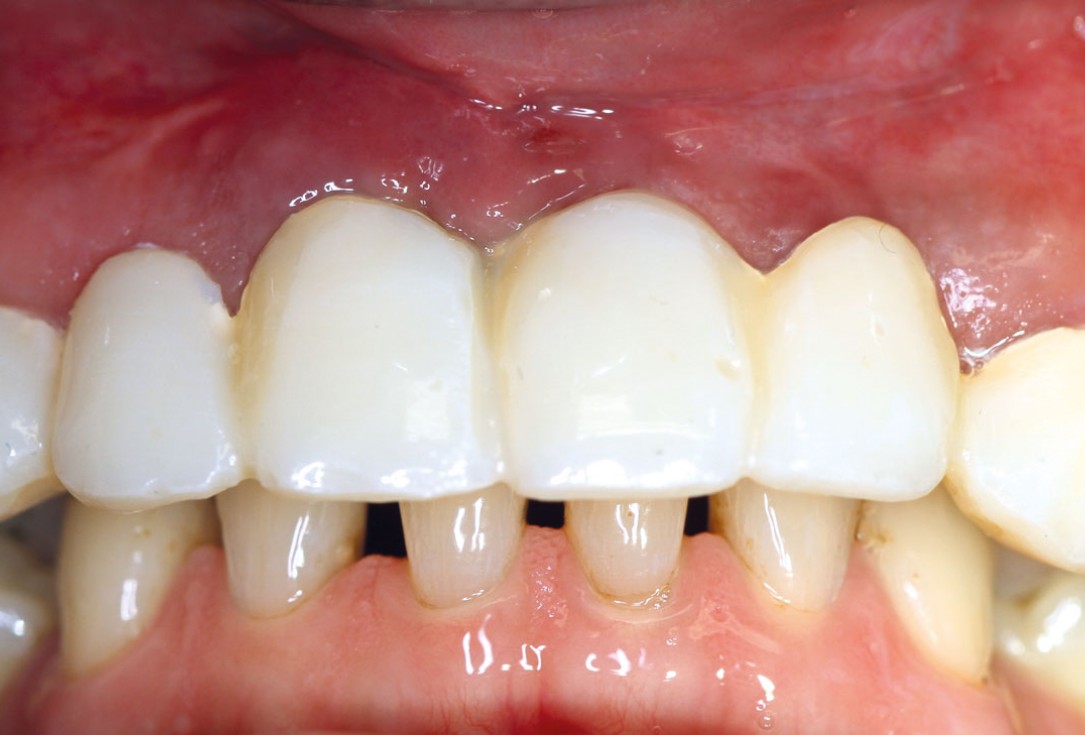

1/17 - Pre-operative clinical situation: changed color in the gingiva in the front maxillaRestoration of all four incisors with maxgraft® bonebuilder - Dr. Dr. Dr. O. Blume

Pre-operative clinical situation: changed color in the gingiva in the front maxilla